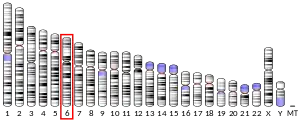

| External IDs | OMIM: 248611 MGI: 88137 HomoloGene: 39 GeneCards: BCKDHB | ||||||||||||||||||||||||||||||||||||||||||||||||||

- Zneimer SM, Lau KS, Eddy RL, et al. (1991). "Regional assignment of two genes of the human branched-chain alpha-keto acid dehydrogenase complex: the E1 beta gene (BCKDHB) to chromosome 6p21-22 and the E2 gene (DBT) to chromosome 1p31". Genomics. 10 (3): 740–7. doi:10.1016/0888-7543(91)90458-Q. PMID 1889817.